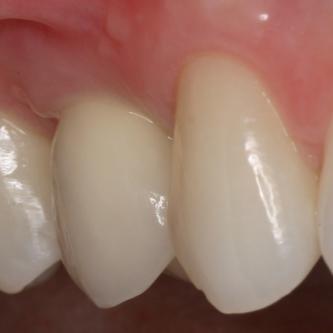

Exemple 3: Un implant à la place d'une incisive latérale supérieure droite. Sur cette image on voit le moignon en titane qui est vissé sur l'implant.

Exemple 3: Puis sur ce moignon, la couronne en céramique est scellée.

Exemple3: La couronne en place.